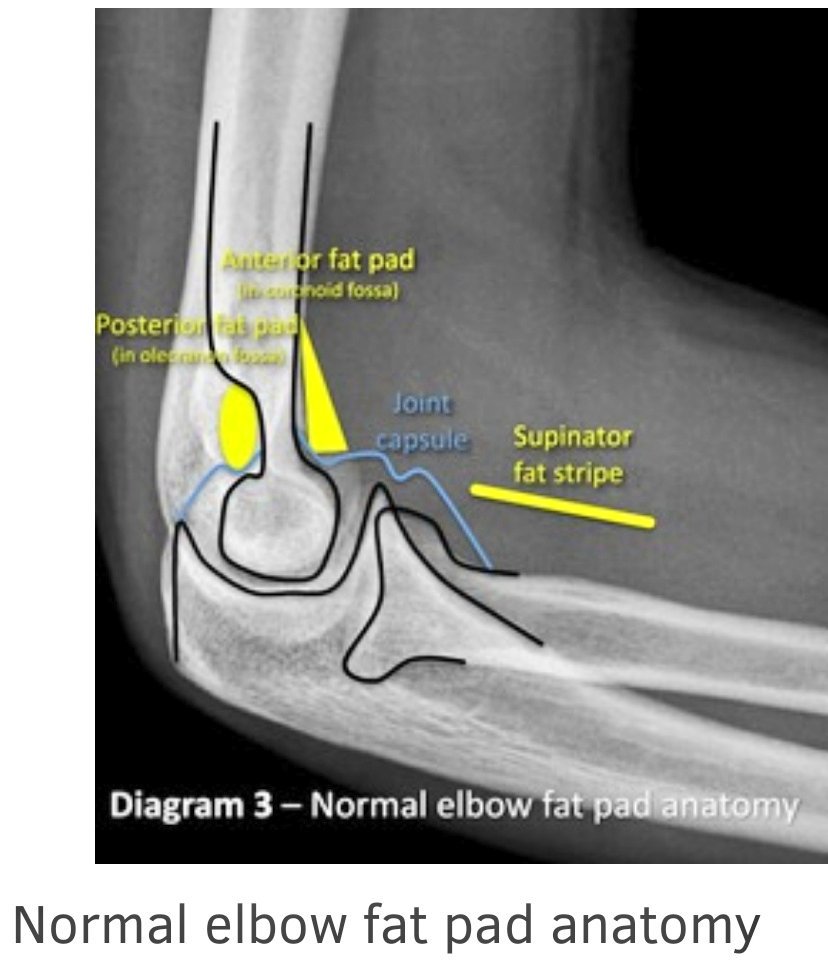

الوضع الجانبي Lat. Elbow

•يعد أهم وضع لتقييم المفصل،لماذا؟

•بسبب ظهور تراكيب تشريحية لا ترى إلا في هذا الوضع.

•هذه التراكيب يتم الاستعانة بها في تقييم حدوث إصابة للمفصل أم لا.

•تسمى fat pads/stripes :

1.supinator fat stripe.

2.Anterior fat pad.

3.posterior fat pad.

Posterior fat pad

لاترى في الوضع الصحيح إلا إذا كان هناك مرض أو إصابة أظت لانزياحها.

لرؤية هذه pads لابد من شروط:

١.أن يكون المفصل مثني ٩٠°.

٢.أن يكون الوضع مطبق بشكل مثالي.

True lateral position.

٣.استخدام عوامل صحيحة (ليست قوية بشكل كبير حتى لانفقد تفاصيل الأنسجة الرخوة).

الوضع Lat. Elbow

•يكون الكتف و الذراع على مستوى الطاولة.

•ثني المرفق بزاوية ٩٠°تماماً.

•وضع الساعد و اليد في true lateral.

السنتر :في منتصف المفصل.

نقد الصورة lat.elbow

•المفصل مثني ٩٠°.

•نصف radial head

مغطاه بواسطة coronoid process.

•يجب أن يظهر olecranon process كاملاً.

•تراكب epicondyles.

•ظهور ٣ أقواس(concentric arcs):

ظهور الثلاثة أقواس يدل على أن الوضع تم بزاوية ٩٠° للمفصل.

هذه الأقواس هي:

1.trochlear sulcus(first and smallest)

2.outer ridges of :capitulum(small arc)and trochlea(large arc).

3.Trochlear notch of Ulna.

●عندما يكون المفصل في وضع غير صحيح فإن هذه الخطوط سيختل ترتيبها.